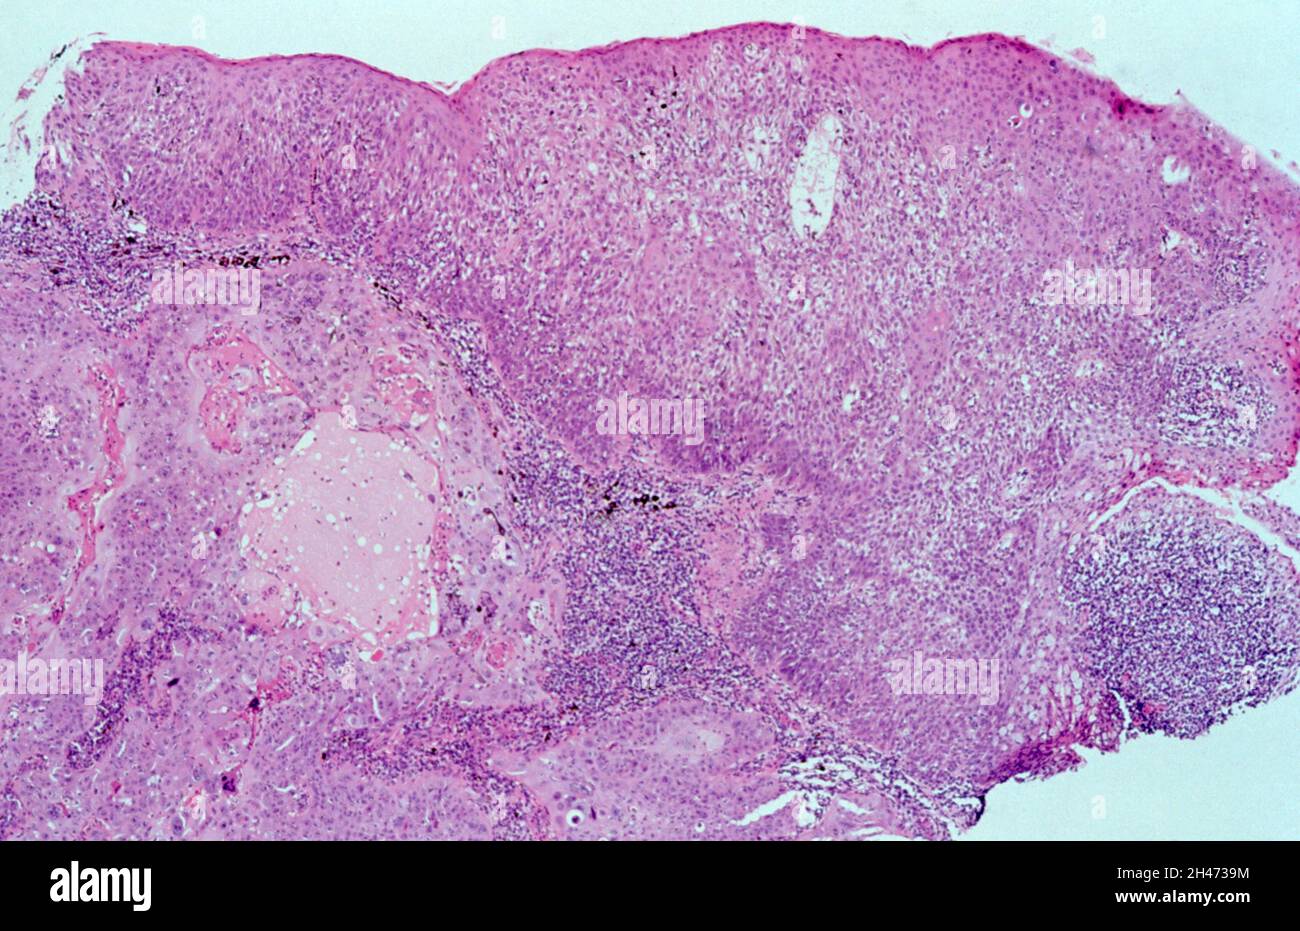

Carcinome Canalaire In Situ De Haut Grade Avec Nécrose

Carcinome canalaire infiltrant. Nécrose tumorale. Download Scientific Diagram. Des critères histologiques comme le haut grade et l'âge jeune de la patiente sont associés à un risque augmenté de 2e CCIS et de CCI homolatéral Le CCIS (carcinome canalaire in situ) concerne environ 20 à 25% des cancers du sein.